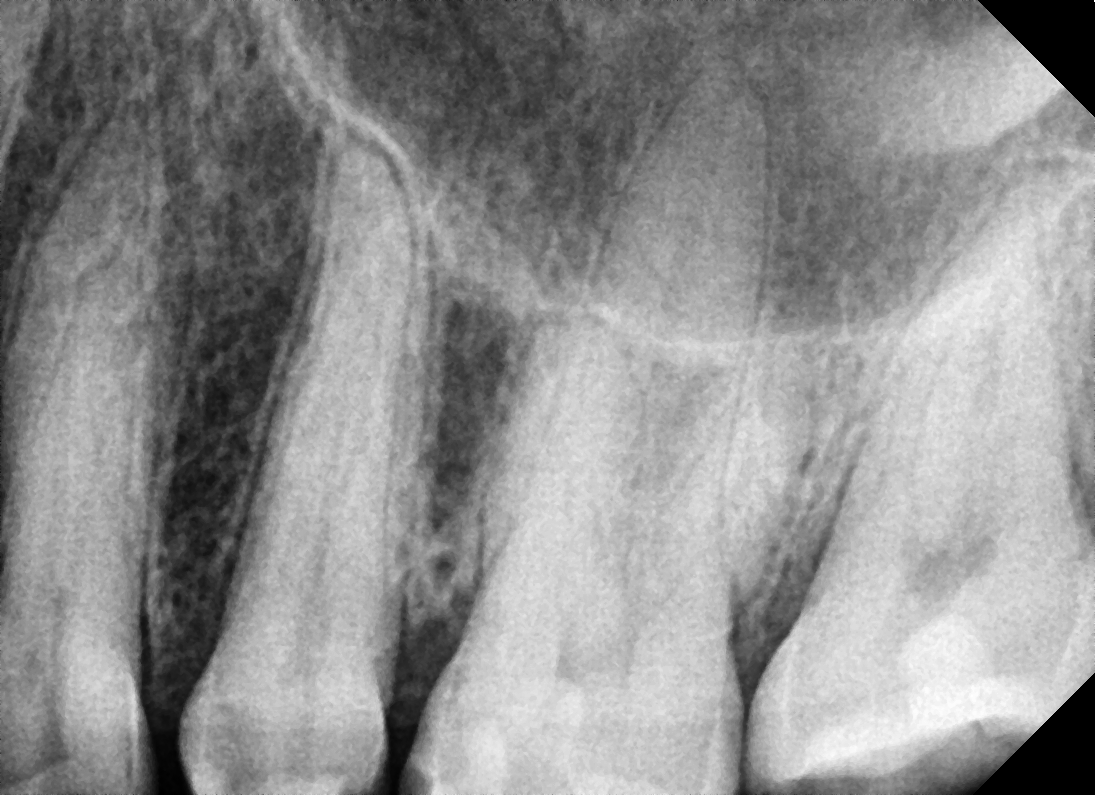

Severe pain and discomfort is going to be one of the problems of not treating the tooth. Without treatment the blood vessels and nerves inside the tooth become severely infected and that’s when pus and abscesses form. An abscess is swelling full of pus usually located at the end of the root canal because of the buildup of the infection. The abscess can be so serious that it causes swelling around the face, eye or the neck.

• A diagnosis is made for the tooth with percussion, palpation and cold tests and an x-ray.

Gallery